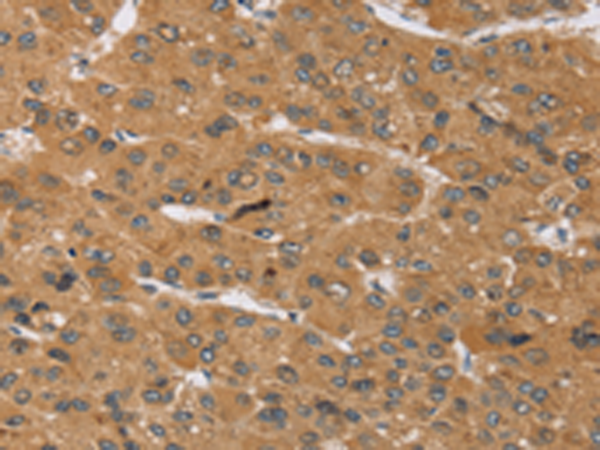

分类: 科研抗体货号: P05227别名: IRKK; KIR1.3; KIR4.2应用: IHC反应种属: Human, Mouse, Rat